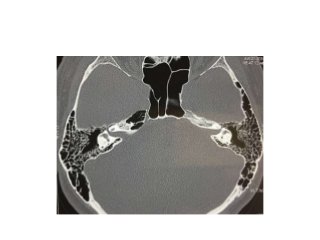

Temporal bone CT. Look at the sub-cochlear canaliculus or sub-cochlear

tunnel that can allow endoscopic transcanal retrocochlear access to the IAC

and drain the petrous apex cells